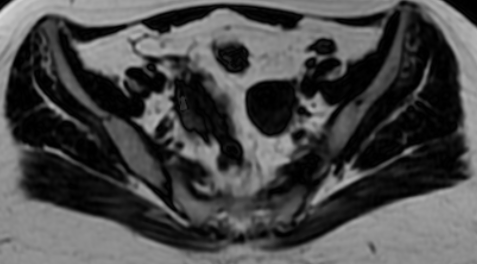

Justo me acaban de mandar un mail con los resultados de mi resonancia... Me encanta que lo tomamos con mucho humor y se hace más llevadero. 😆

No entendemos el informe porque tiene muchas palabras técnicas, pero mañana me verá el doctor de nuevo. 🫡

¿Ustedes que forma ven? 😅

Yo veo un murciélago, un diavlo y una paleta payaso.

Español